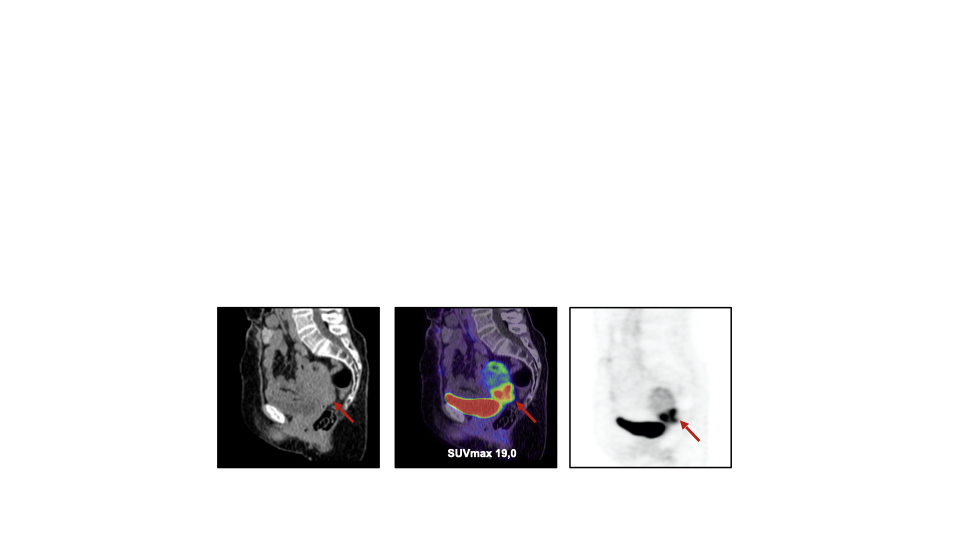

PURPOSE : 68Ga-FAPI (fibroblast activation protein inhibitor) is a novel and highly promising radiotracer for PET/CT imaging. The aim of this retrospective analysis is to explore the potential of FAPI-PET/CT in gynecological malignancies. We assessed biodistribution, tumor uptake, and the influence of pre- or postmenopausal status on tracer accumulation in hormone-sensitive organs. Furthermore, a comparison with the current standard oncological tracer 18F-FDG was performed in selected cases. PATIENTS AND METHODS : A total of 31 patients (median age 59.5) from two centers with several gynecological tumors (breast cancer; ovarian cancer; cervical cancer; endometrial cancer; leiomyosarcoma of the uterus; tubal cancer) underwent 68Ga-FAPIPET/ CT. Out of 31 patients, 10 received an additional 18F-FDG scan within a median time interval of 12.5 days (range 1–76). Tracer uptake was quantified by standardized uptake values (SUV)max and (SUV)mean, and tumor-to-background ratio (TBR) was calculated (SUVmax tumor/ SUVmean organ). Moreover, a second cohort of 167 female patients with different malignancies was analyzed regarding their FAPI uptake in normal hormone-responsive organs: endometrium (n = 128), ovary (n = 64), and breast (n = 147). These patients were categorized by age as premenopausal (<35 years; n = 12), postmenopausal (>65 years; n = 68), and unknown menstrual status (35–65 years; n = 87), followed by an analysis of FAPI uptake of the pre- and postmenopausal group. RESULTS : In 8 out of 31 patients, the primary tumor was present, and all 31 patients showed lesions suspicious for metastasis (n = 81) demonstrating a high mean SUVmax in both the primary (SUVmax 11.6) and metastatic lesions (SUVmax 9.7). TBR was significantly higher in 68Ga-FAPI compared to 18F-FDG for distant metastases (13.0 vs. 5.7; p = 0.047) and by trend for regional lymph node metastases (31.9 vs 27.3; p = 0.6). Biodistribution of 68Ga-FAPI-PET/CT presented significantly lower uptake or no significant differences in 15 out of 16 organs, compared to 18F-FDG-PET/CT. The highest uptake of all primary lesions was obtained in endometrial carcinomas (mean SUVmax 18.4), followed by cervical carcinomas (mean SUVmax 15.22). In the second cohort, uptake in premenopausal patients differed significantly from postmenopausal patients in endometrium (11.7 vs 3.9; p < 0.0001) and breast (1.8 vs 1.0; p = 0.004), whereas no significant difference concerning ovaries (2.8 vs 1.6; p = 0.141) was observed. CONCLUSION : Due to high tracer uptake resulting in sharp contrasts in primary and metastatic lesions and higher TBRs than 18F-FDGPET/ CT, 68Ga-FAPI-PET/CT presents a promising imaging method for staging and follow-up of gynecological tumors. The presence or absence of the menstrual cycle seems to correlate with FAPI accumulation in the normal endometrium and breast. This first investigation of FAP ligands in gynecological tumor entities supports clinical application and further research in this field.